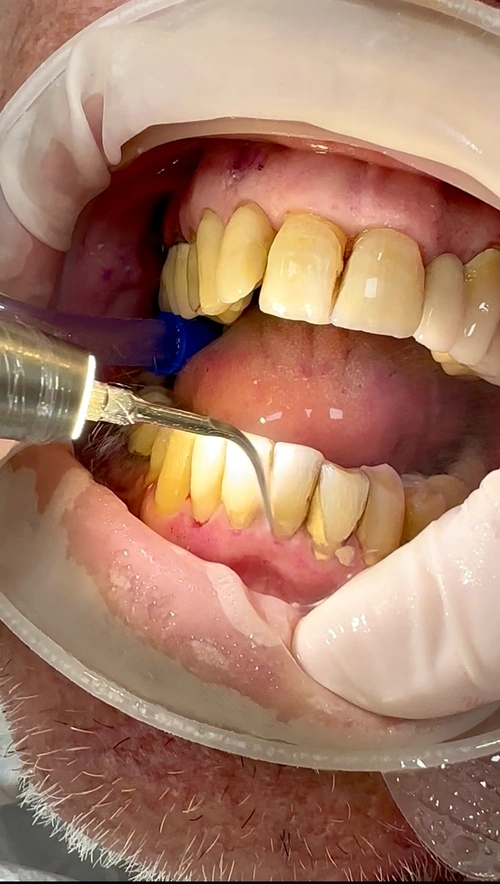

O tratamento começa com a remoção cuidadosa das placas bacterianas e do tártaro, utilizando técnicas minimamente invasivas para evitar traumas na área já inflamada.

Pensando em sempre entregar aos meus pacientes técnicas minimamente invasivas e o que há de melhor e mais moderno na odontologia, com tratamento de alto padrão e pós tratamento com conforto e maior qualidade, resolvi abraçar uma nova tecnologia, o PIEZO Ultrassônico.

Um aparelho de ultrassom que cirurgicamente não corta tecidos moles, vasos sanguíneos, nervos e membranas e, assim, mantém a gengiva do paciente intacta e sem sangramento, dando suavidade, muita precisão e segurança. Reduz traumas porque há menor chance de aquecimento e edemas, possibilitando maior conforto e um curto prazo de recuperação.

As pontas ultrassônicas para remoção de tártaro, por exemplo, são constituídas por pequenas pedras de diamantes coladas a uma haste de metal, que amortecem o impacto da vibração do aparelho na boca, tornando o procedimento quase sem percepção pelo paciente.